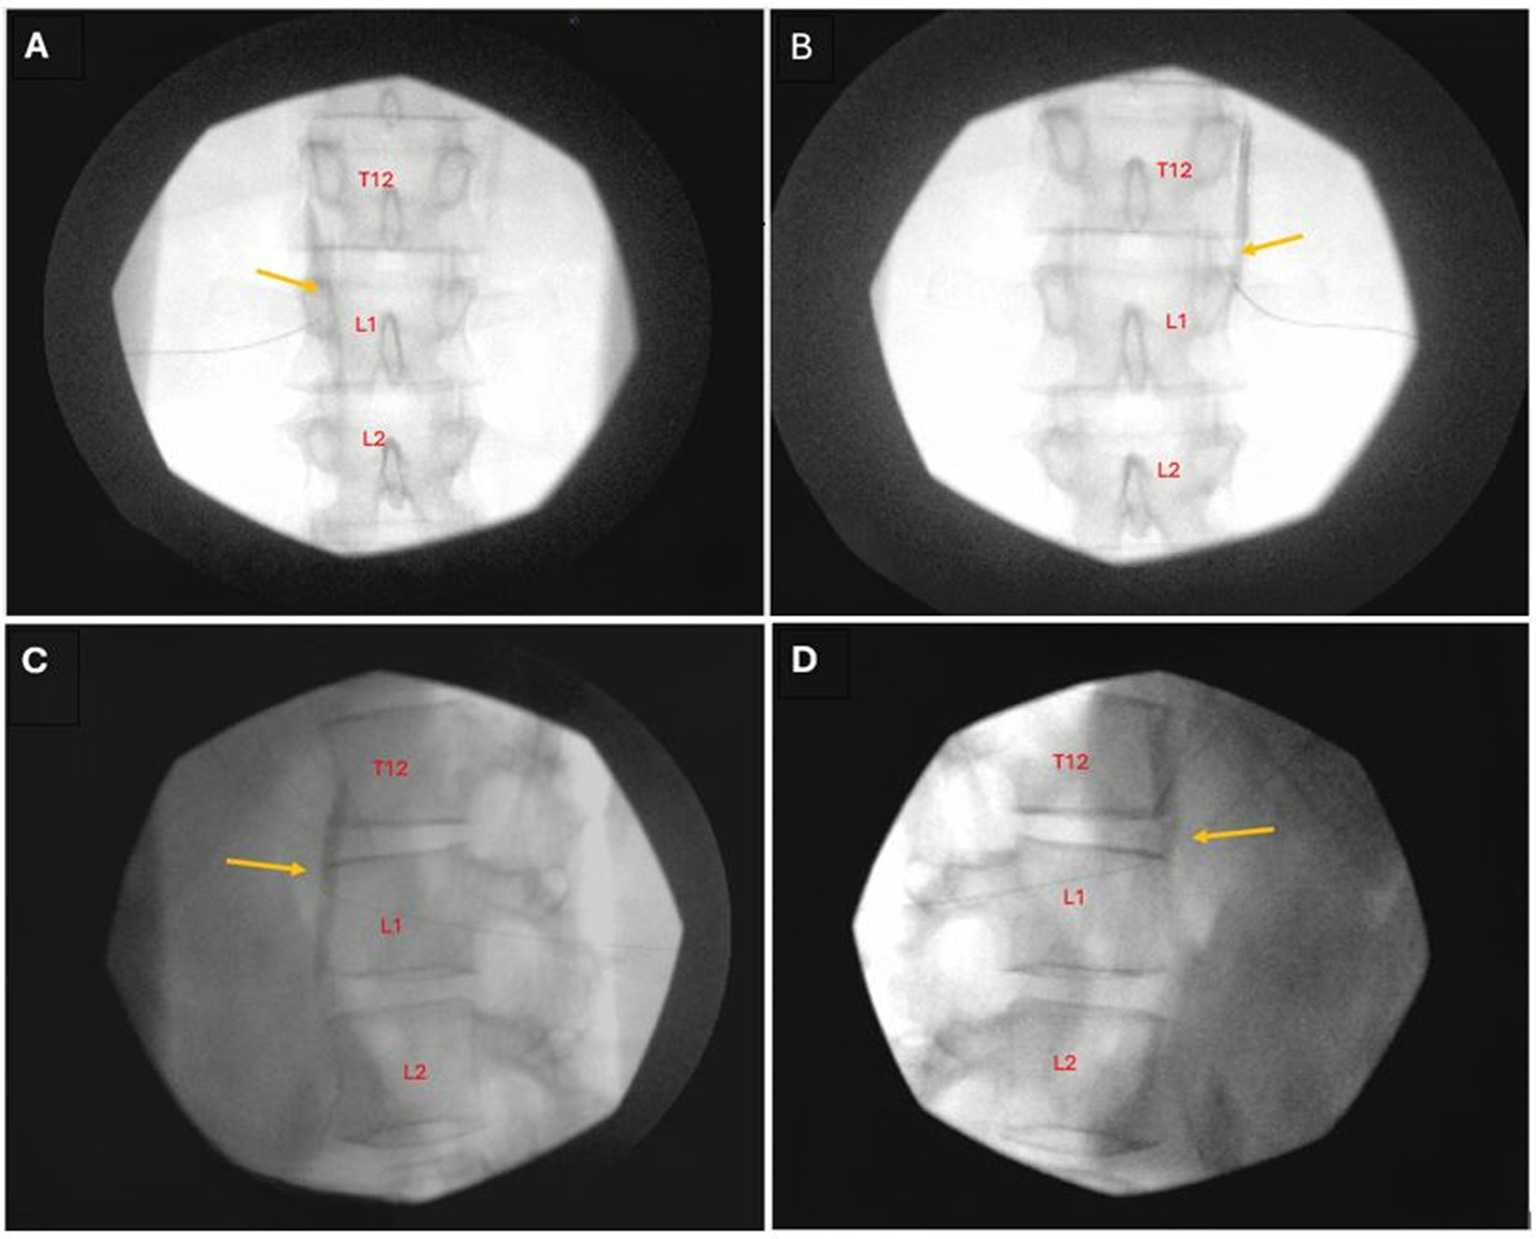

Lingering symptoms following SARS-CoV-2 infection, recognized as the clinical entity "Long COVID", are common. Gastrointestinal dysfunction during and after COVID have received little attention to date and remain largely unaddressed. We have previously shown that numerous symptoms of Long COVID excluding gastrointestinal symptoms improve or resolve following stellate ganglion blocks (SGB). Here, we are first to report successful treatment of persistent post-COVID epigastric pain and diarrhea in three patients using celiac plexus block, a procedure commonly used for visceral abdominal pain and implicating the autonomic nervous system in Long COVID-associated GI symptoms.